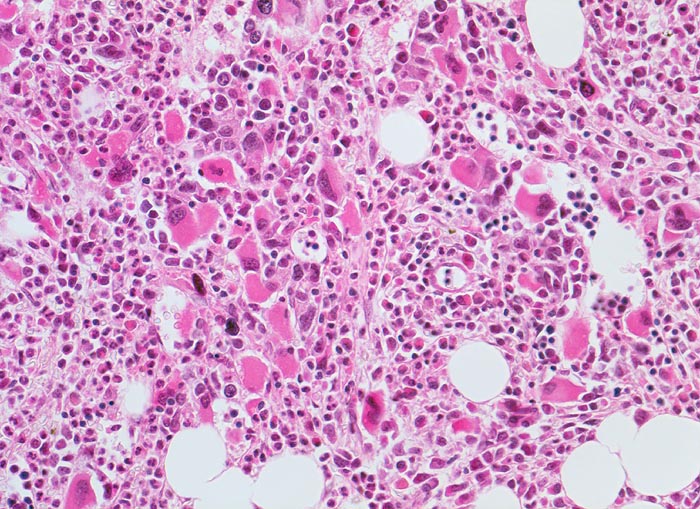

PathoPic – image database / PathoPic ID 3907 - Primäre Myelofibrose (PMF)

Primäre Myelofibrose (PMF)

Vermehrung von atypischen in Gruppen liegenden Megakaryozyten in perisinusoidaler Position. Typisch ist die intravasale Hämopoese in dilatierten Sinusoiden. Hyperplasie von ausreifenden Granulozyten. Erythropoese hypoplastisch. Durch die Fibrose entsteht der Eindruck von strömenden Zellen.

Die Megakaryozyten sind bei der primären Myelofibrose deutlich vermehrt und bilden oftmals Haufen. Sie zeigen eine deutliche Reifungsstörung mit hypolobulierten chromatindichten Kernen und Grössen zwischen Riesen- und Mikroformen (nackte Megakaryozytenkerne ohne Zytoplasma).